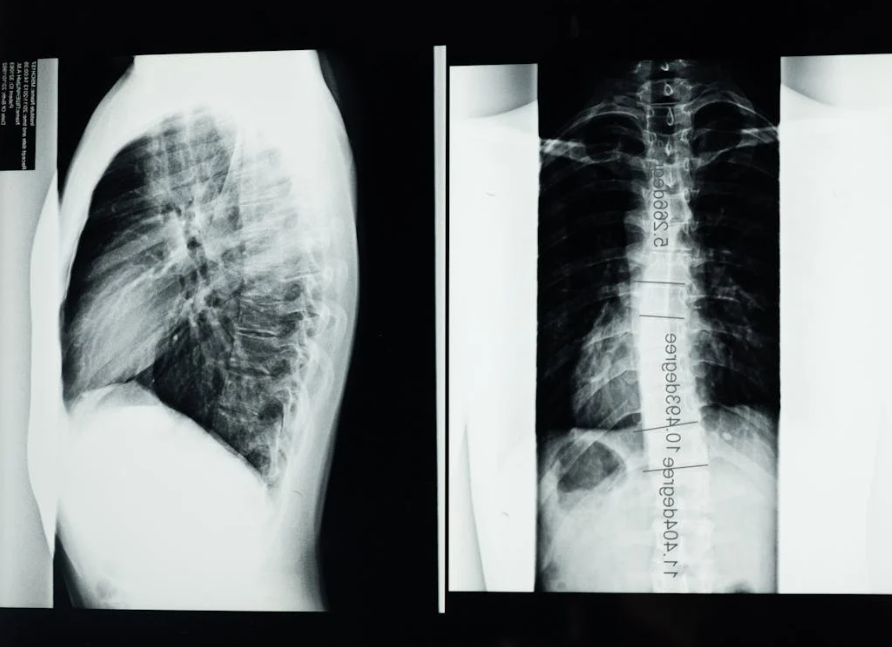

허리 디스크는 신체검사와 함께 MRI, CT, X-ray 등 영상 검사를 통해 진단합니다. 특히 MRI는 디스크 상태와 신경 압박 정도를 정확히 확인할 수 있어 가장 널리 사용됩니다.